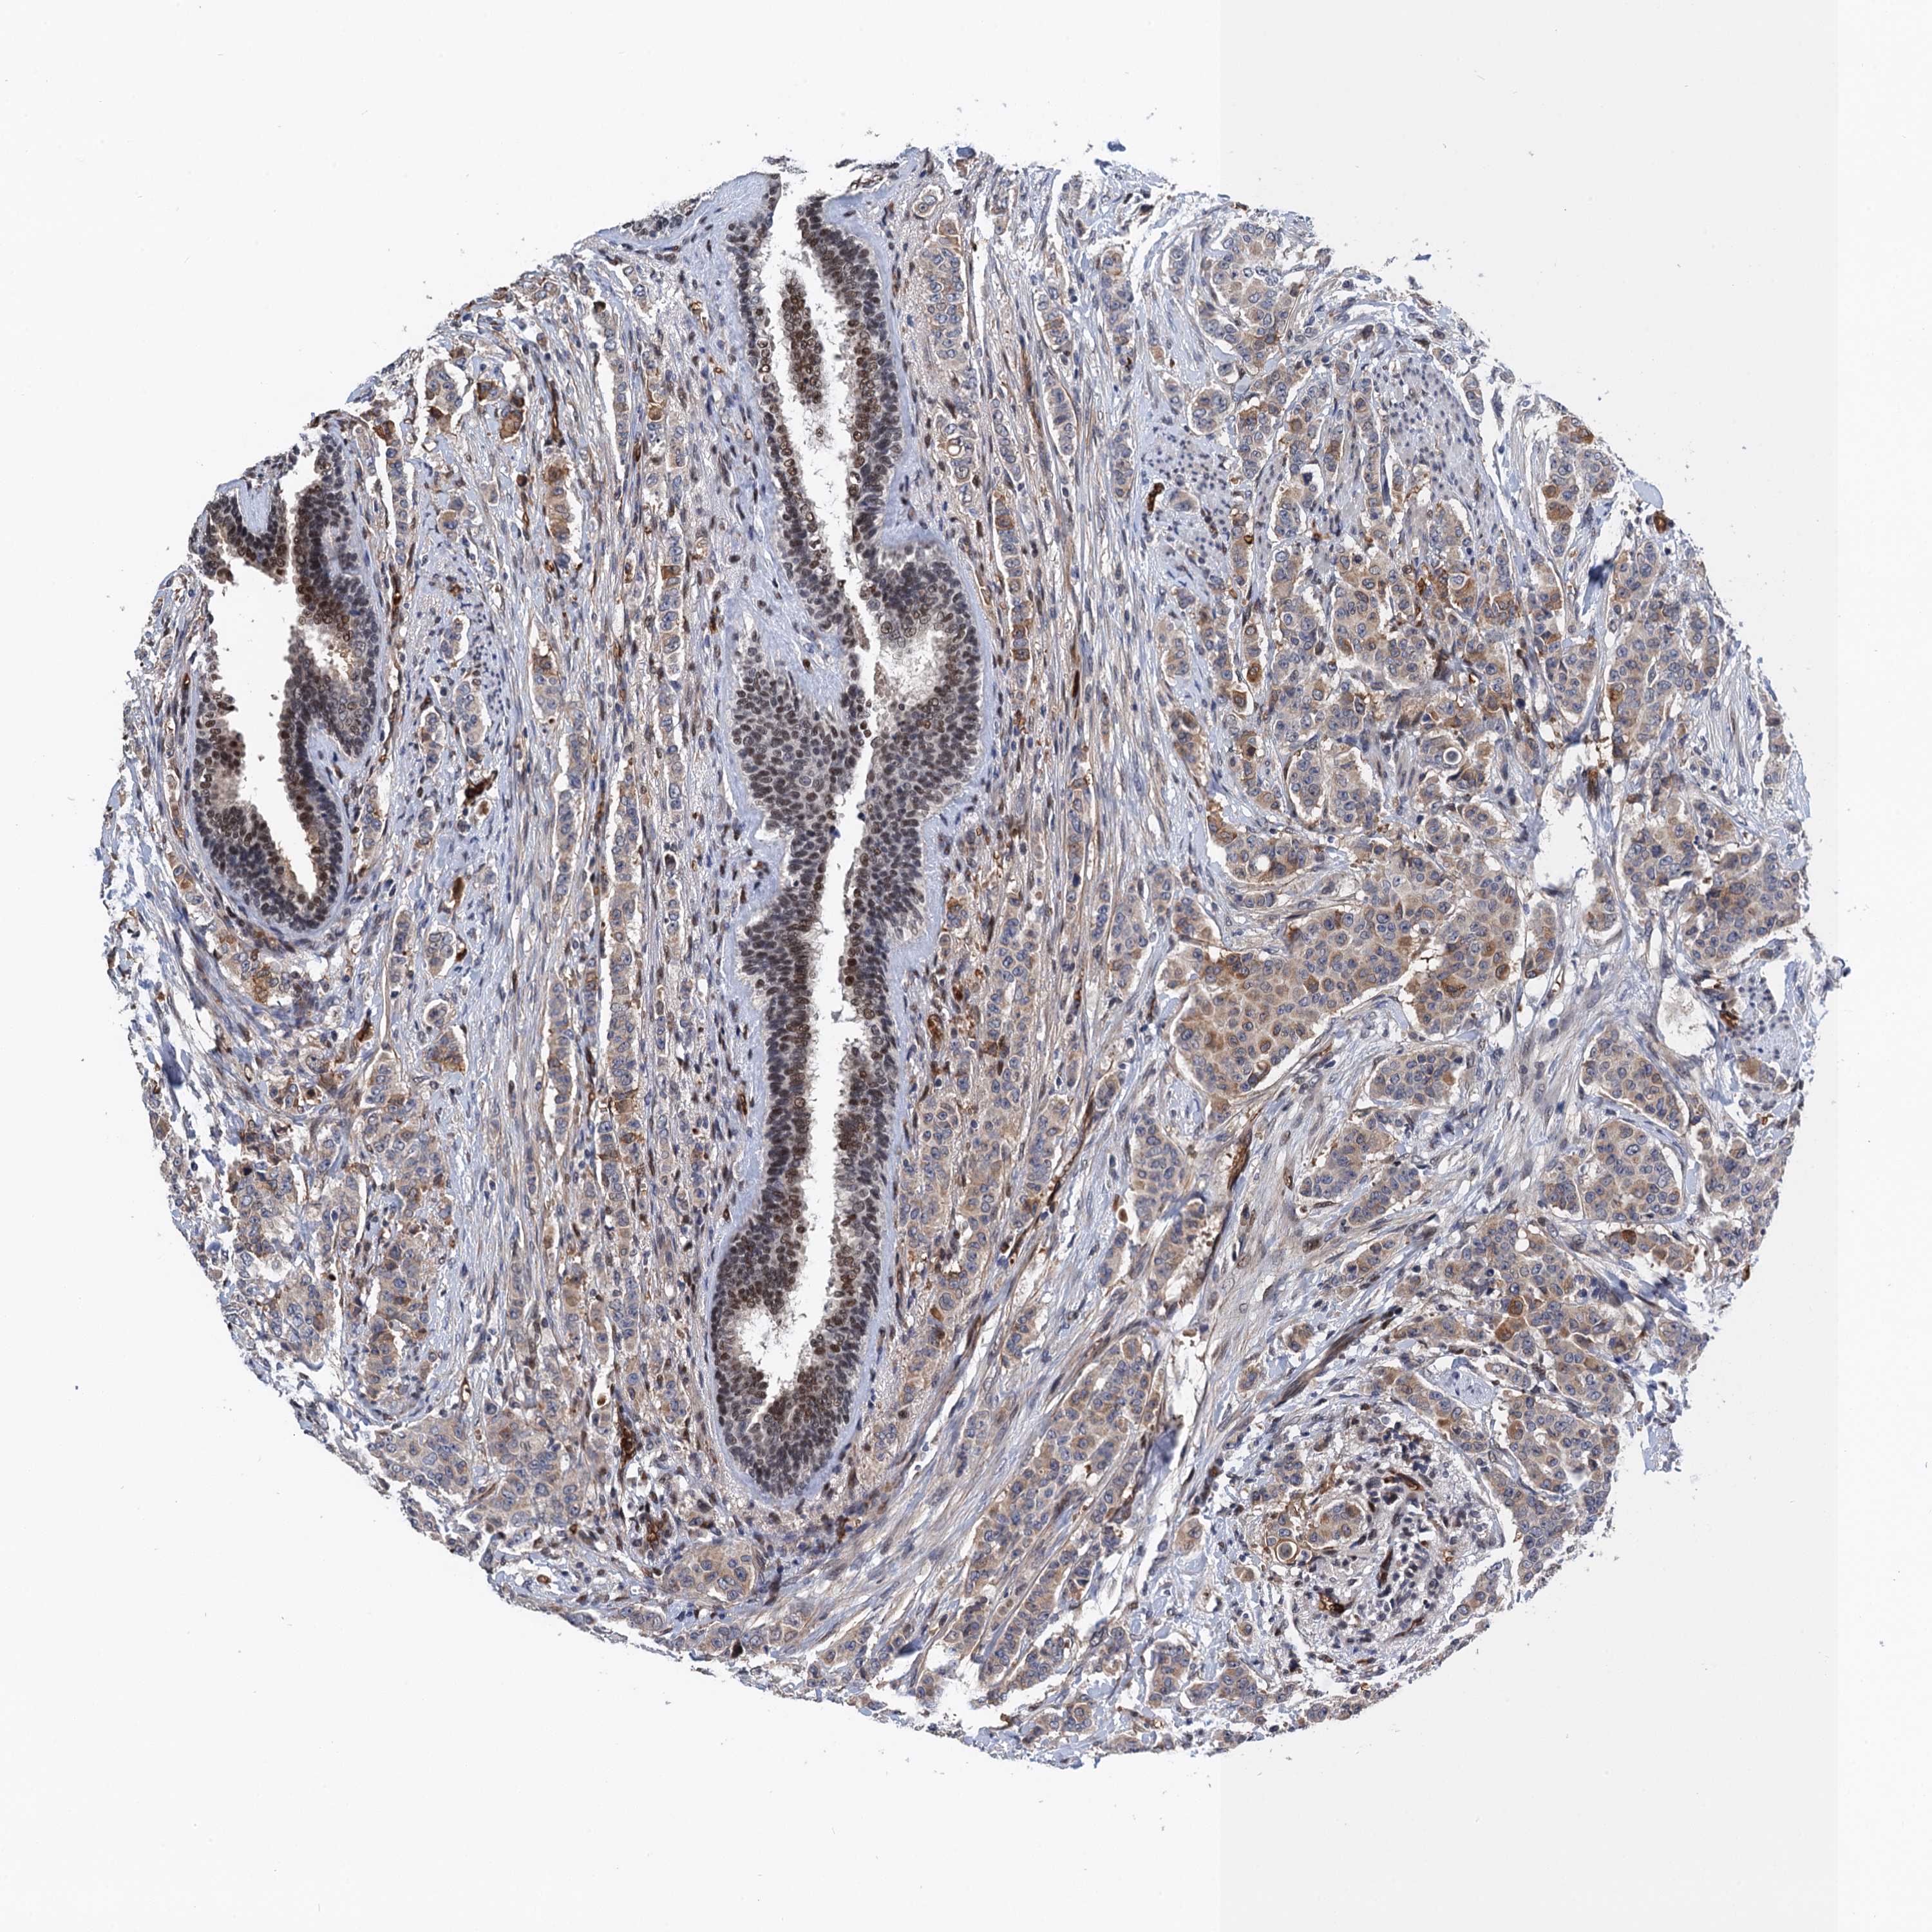

CANCER BREAST CANCER Show tissue menu

BRCA TCGA BRCA VALIDATION PROTEIN EXPRESSION

ANTIBODIES

AND

VALIDATION